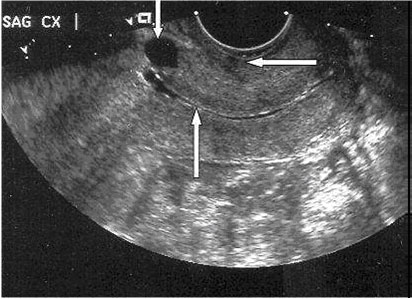

Areas of Increased Echogenicity in the Outer Layer With or Without Myometrial Thinning :

In some patients, the previous scar was identified as an isolated thickened echogenic area in the outer layer, whereas the myometrial layer underneath this area appeared asymmetrically thinned out when compared with the adjacent myometrium.